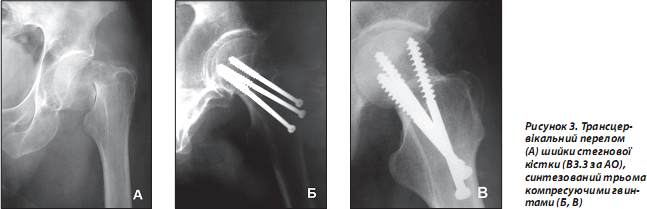

Досягти позитивних результатів оперативного втручання допомагає використання сучасної рентгенослідкуючої апаратури та ретельне дотримання вимог одномоментної репозиції за рекомендованих методик [4, 13, 15]. Гвинти повинні бути відповідної довжини та вводитись у вигляді рівностороннього трикутника при перетинанні ШСК. Нижній гвинт обов’язково (особливо при остеопорозі) слід проводити дотично до дуги Адамса. Різьбовий кінець гвинта не повинен наближатися до субхондральної замикальної пластинки головки стегнової кістки менше ніж на 6–10 мм. Другий і третій шурупи проводяться проксимальніше, паралельно першому та дозволяють запобігти виникненню дорзальної дислокації і ротації головки. Головки гвинтів або опірні шайби повинні впиратись у підвертлюговий компактний шар стегнової кістки з ретельним почерговим догвинчуванням для створення міжфрагментарної компресії (рис. 3).